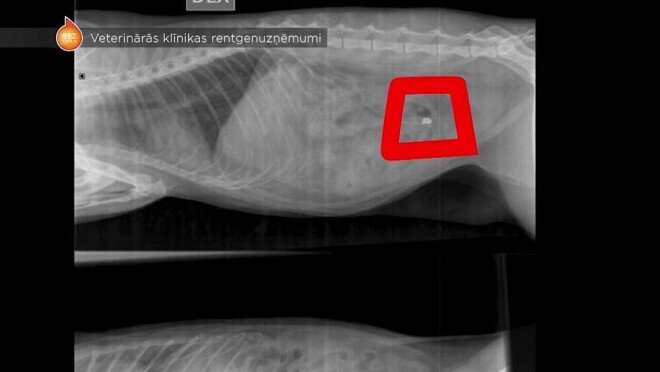

Кот Василий убежал со двора, и только на следующий день семья застала его спящим на территории. Тогда стало ясно, что нужна помощь ветеринаров. Семья отвезла кота в клинику, где сделали рентген. По фотографиям видно, что в теле кота пуля.

Врачи клиники посоветовались и решили не удалять пулю с тела, так как это может травмировать кота, но Василия госпитализировали для наблюдения за его здоровьем. "Мы обратились в Кенгарагский участок Государственной полиции, приложили выписку из ветеринарной клиники, а также рентгеновские снимки, на которых видно, что у кота пуля. Месяц спустя мы начали интересоваться, выяснилось, что через три дня после написания заявления полиция уже приняла решение не возбуждать уголовное дело, а нас об этом даже не уведомили. Полиция не допросила стреляющего и свидетелей. Сказал, что нет состава преступления, т.к. с котом все в порядке", - возмущенно рассказывает хозяйка кота.

Ветеринар Илга Лейкума отрицает, что кто-то из коллег сказал бы, что от выстрела осталась только царапина. "Если пуля уже в теле, я не знаю, можно ли это все назвать царапиной. Вряд ли. Стрельба по домашним животным запрещена, это опасно. Один миллиметр в сторону - и будет поврежден жизненно важный орган", - отмечает ветеринар.